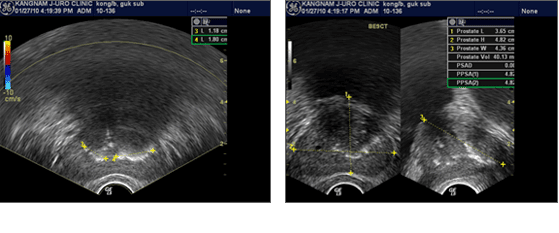

¾ç¼º Àü¸³¼±ºñ´ëÁõ Ȧ·¾(HoLEP) ¼ö¼ú Àü °Ë»ç Ç׸ñ

¿äµµÇùÂø Ȧ·¾(HoLEP)¼ö¼ú Àü °Ë»ç Ç׸ñ

Àü¸³¼±°á¼® Ȧ·¾(HoLEP)¼ö¼ú Àü °Ë»ç Ç׸ñ

¹æ±¤°á¼® Ȧ·¾(HoLEP)¼ö¼ú Àü °Ë»ç Ç׸ñ